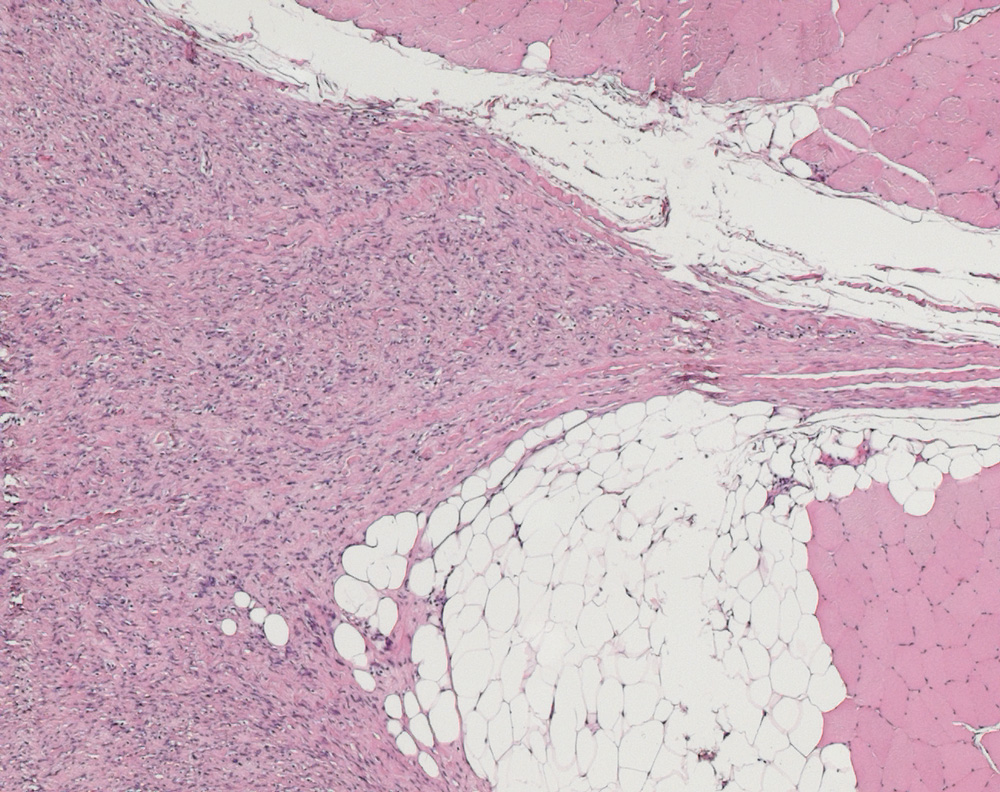

Il perinevrio costituisce il rivestimento di tessuto connettivo intermedio di un nervo periferico e delimita i fasci di fibre nervose.

È uno strato di tessuto connettivo denso più esiguo rispetto all'epinevrio. La parte più interna del perinervio è delimitata da vari strati concentrici (all'incirca 7-8) di fibroblasti disposti in assetto epitelioide, collegati tra loro da zonulae occludentes e gap junction e rivestiti da una lamina basale.

Tra gli strati cellulari si dispongono in senso longitudinale fibre collagene e scarse elastiche. Lo spessore del perinevrio si assottiglia man mano che procede la ramificazione del nervo, fino a ridursi nelle ramificazioni più piccole a un sottile strato di cellule appiattite.